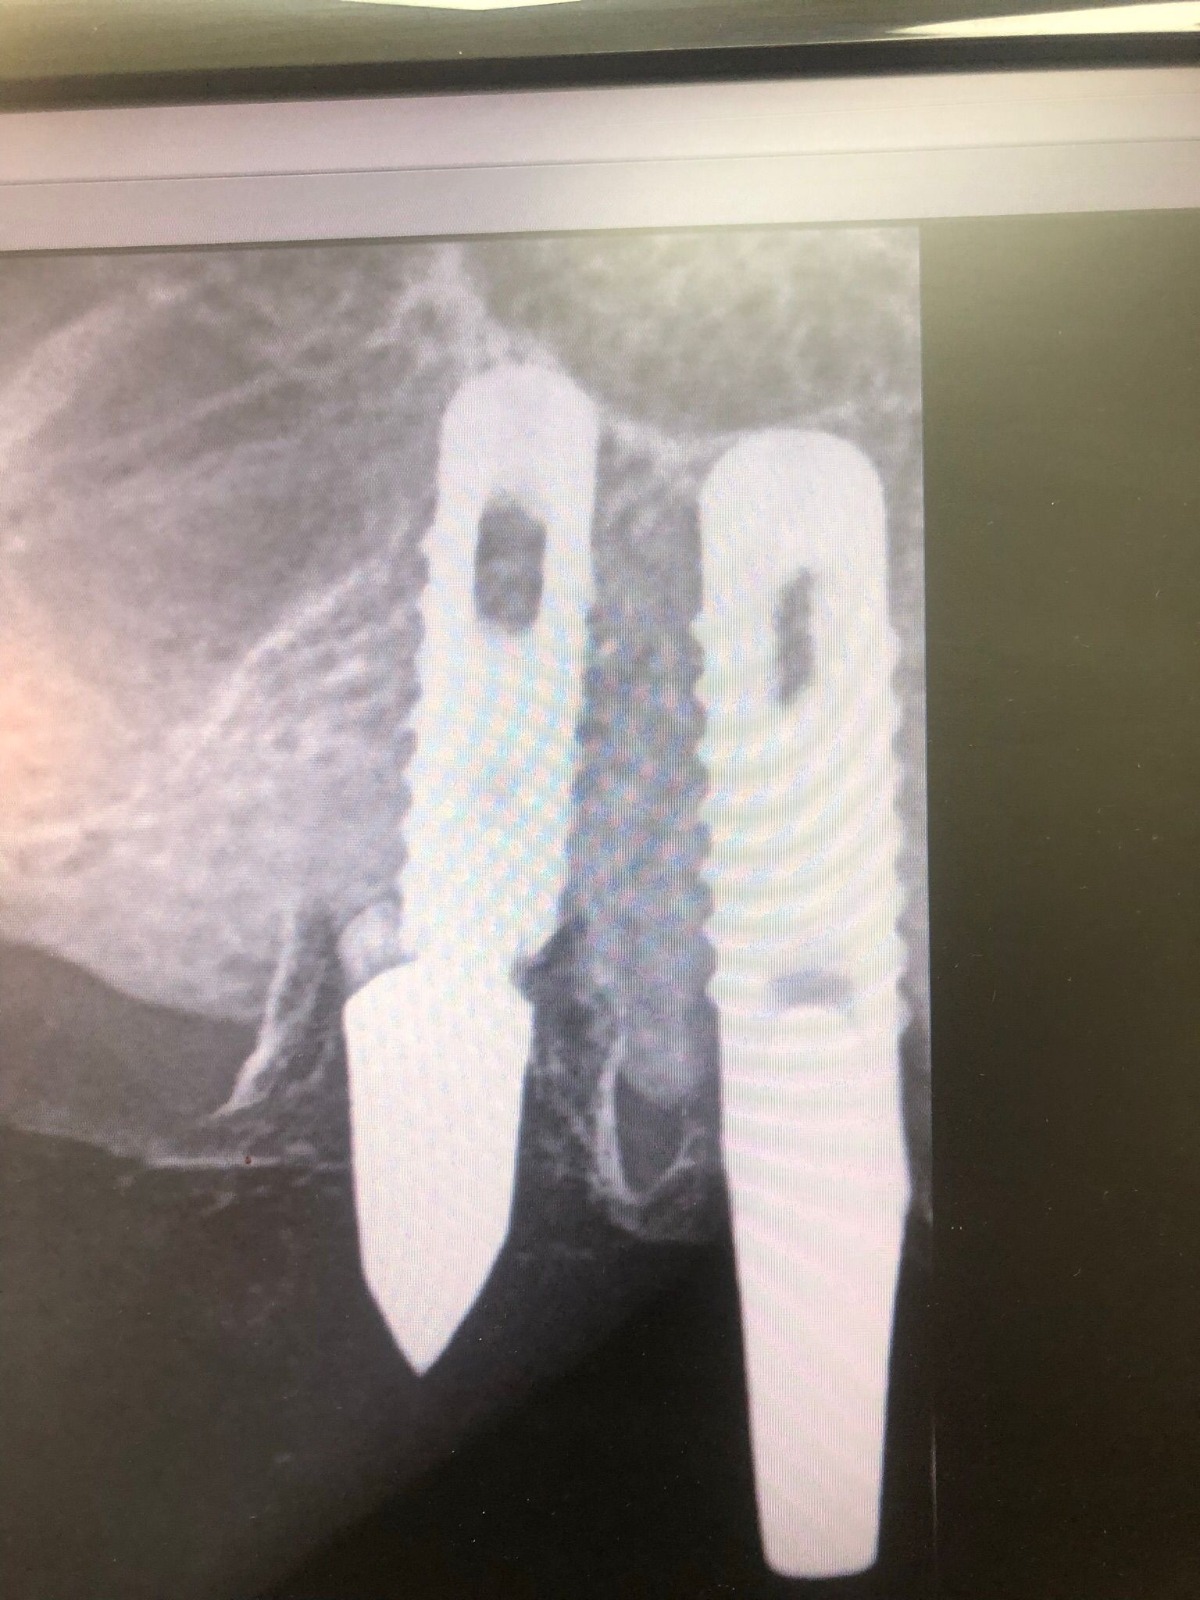

Actualmente vuelve el paciente de nuevo con la misma prótesis. Había roto dos de los tres pilares en concreto los más distales. El primero de los dos había roto la rosca del aditamento dentro del implante como ocurre habitualmente. Pero el ultimo pilar había roto directamente la cabeza del implante tal como se ve en la radiografía y lo que quedaba era un cilindro de titanio macizo perfectamente integrado en el maxilar, sin posibilidad de enroscar nada. Le explicamos al paciente que habría que quitar y poner un implante en el mismo acto. El paciente dijo que no, así que decimos que no se haría cirugía. Buscamos solución alternativa: hacemos un un agujero en el centro del macizo cilíndrico del implante roto y pasamos sucesivamente el set de machos roscantes. Utilizamos una fresa cañón de 1 mm que poco a poco se va introduciendo hasta 8mm con un poco de vagación, que hace que sea un poco mas de 1mm de diámetro. Posteriormente pasamos el conjunto de machos roscantes de métrica 2mm para poder usar un aditamento experimental, que era un palo de rosca de diámetro 2 mm unido a un cuerpo metálico en forma de sombrero napoleónico fabricado en cromo/cobalto, prototipos primitivos de la sistemática ASATIM y que tienen la característica de tener gran resistencia a la fractura. Nos llevó un tiempo largo el tallado de dichos aditamentos, tal como se puede observar en las imágenes, y tras cicatrizar la encía se le hizo una prótesis estándar. Esperemos que no lo rompa más veces.